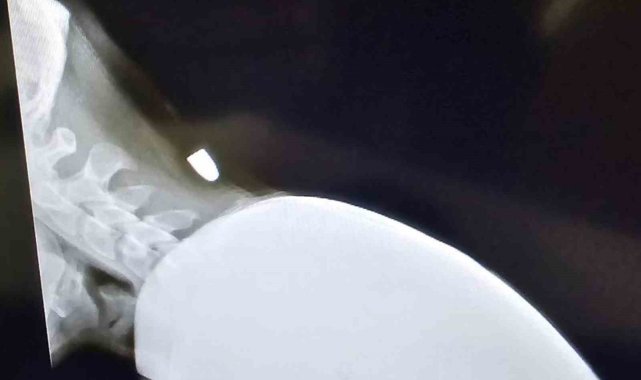

Hatay'ın Kırıkhan ilçesinde yorgun merminin ensesine isabet ettiği 18 yaşındaki Yunus Emre Yavuz, geçirdiği ameliyat ve gördüğü tedavinin ardından taburcu edildi. İş yerinde arkadaşlarıyla oturduğu esnada mermi isabet eden Yavuz, şah damarına 2 santimetre mesafeye isabet eden mermiyle ölümden döndü.Kırıkhan ilçesi Mimar Sinan Mahallesi'nde yaşayan 18 yaşındaki Yunus Emre Yavuz, işyerinde çalıştığı esnada mola vererek arkadaşlarıyla dinlenmeye başladı. Arkadaşlarıyla sohbet ettiği esnada öne doğru eğilen Yavuz'un ensesine nereden geldiği belli olmayan mermi isabet etti. Aniden ensesinde ağrı hisseden Yavuz, yere yığılmasıyla arkadaşları tarafından hastaneye götürüldü. Hastanede yapılan müdahalelerde Yavuz'a ensesine mermi isabet ettiği tespit edildi. Geçen Pazartesi günü ameliyat olan Yavuz'un ensesindeki mermi 40 dakikalık ameliyatla çıkarıldı. Hastaneden taburcu edilen Yavuz'un sağlık durumu gün geçtikçe iyiye gidiyor. Polis ekipleri de konuyla ilgili inceleme başlattı."Eğildiğim anda merminin düşmesi bir oldu ve sanki biri sertçe sopayla vurmuş gibi hissettim"Arkadaşlarıyla otururken yorgun merminin isabet ettiğini dile getiren Yunus Emre Yavuz, "İşte çalışıyorduk ve mola verdik. Akşam 19:30 sularında otururken biraz eğildim. Eğildiğim anda merminin düşmesi bir oldu. Biri sanki sertçe sopayla vurmuş gibi hissettim. Arkadaşlar yaraya baktığında kurşun olduğunu gördüler. Hastaneye götürdüler. Röntgen ve filmlere bakıldığında mermi olduğu anlaşıldı. Hastane sürecinde; röntgen ve MR filmleri çekildikten sonra ameliyat olmalısın dediler. Geçen pazartesi ameliyata girdim ve 40 dakika sürdü. Şükürler olsun sağlam çıktım. Kurşunu da incelenmesi için Adana'ya gönderildi. Zorlu bir süreç oldu ama atlattık" dedi."Kurşun şah damarının 2 cm yanındaydı, biraz daha derine inseydi felç kalacaktım veya morgda olacaktım"Merminin şah damarının 2 santimetre yakınına isabet ettiğini Yavuz, "Ölümden döndüm. Ben değil başkası da olabilirdi veya ölebilirdim. Ben ölmedim ama başkasının başına gelip ölebilirdi. Kurşun şah damarının 2 cm yanındaydı ve biraz daha derine inseydi felç kalacaktım veya morgda olacaktım. Çocukluk hayalim asker olmaktı. Astsubay sınavları için hazırlanıyordum ki yorgun mermi başıma geldi. Kurşun izi kaldığı için askerlik hayalim tehlikeye girecek. Çocukluk hayalim olan astsubaylık askerlik hayatım yorgun mermi yüzünde bitti" ifadelerini kullandı.